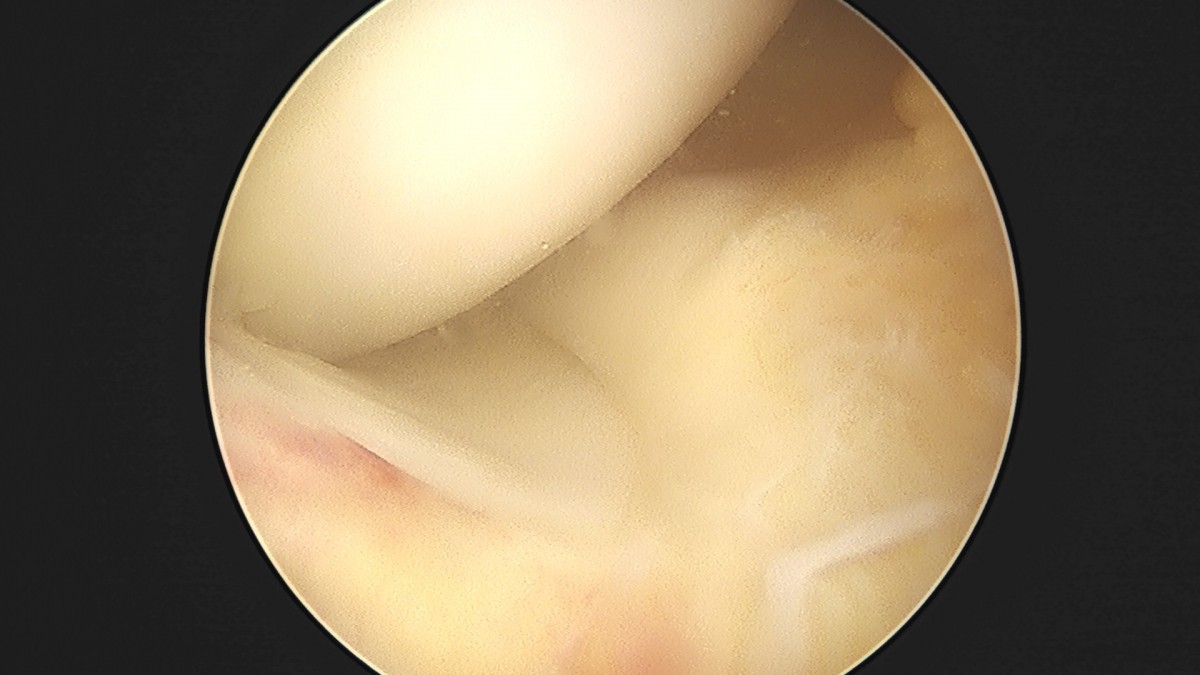

이재상원장님 전방십자인대 재건술 및 반월상 연골판 봉합술 윤두O 환자

dae765e4d9ac96aee867c9d6292d8784_1758007347_8387.jpg